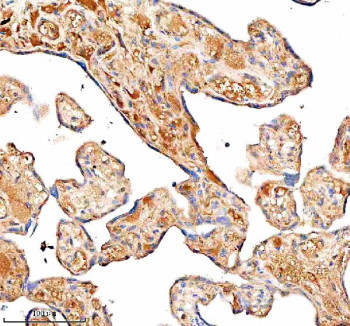

Adding 0.2 ml of distilled water will yield a concentration of 500 ug/ml. C1 Inhibitor (C1-INH) Antibody recognizes a secreted serine protease inhibitor encoded by the SERPING1 gene, which is essential for controlling complement activation and vascular permeability. Although the predicted molecular weight is ~55 kDa, the mature glycoprotein migrates near 100-105 kDa due to extensive N-linked glycosylation. C1 Inhibitor, also known as C1 esterase inhibitor or plasma protease C1 inhibitor, is synthesized mainly by hepatocytes and secreted into the plasma where it inactivates the complement proteases C1r and C1s. This regulation prevents uncontrolled complement activation and protects tissues from inflammatory damage. The protein is part of the serpin superfamily and contributes to immune, vascular, and coagulation homeostasis through its inhibition of multiple serine proteases.The C1 Inhibitor (C1-INH) Antibody detects a multifunctional protein that serves as a critical regulator of both the complement and contact systems. By inhibiting kallikrein and factor XIIa, C1 inhibitor controls bradykinin release, preventing excessive vasodilation and edema formation. Genetic or acquired deficiency of SERPING1 leads to hereditary angioedema (HAE), an autosomal dominant disorder characterized by recurrent subcutaneous and submucosal swelling episodes. In these patients, reduced or dysfunctional C1 inhibitor fails to block complement activation and bradykinin formation, causing fluid extravasation and tissue swelling. The proteinâ?(TM)s physiological importance extends beyond the complement system, influencing inflammation, coagulation, and endothelial permeability.C1 inhibitor belongs to the serpin family of irreversible protease inhibitors, sharing structural similarities with alpha-1 antitrypsin and antithrombin III. It contains a conserved serpin domain with a reactive center loop that inserts into its own beta-sheet following protease binding, trapping and inactivating the enzyme. This mechanism results in the formation of stable covalent complexes visible as higher molecular weight species on western blot. The proteinâ?(TM)s extensive glycosylation accounts for its diffuse migration and apparent mass variation between 90 and 105 kDa. Treatment with PNGase F collapses the heterogeneity, confirming glycan modification as the major cause of the migration shift. The protein is synthesized in the endoplasmic reticulum and Golgi before secretion and functions primarily in extracellular plasma compartments.C1 inhibitor expression is highest in the liver but also found in endothelial cells, monocytes, macrophages, and astrocytes. Local expression in the vascular endothelium contributes to regulation of complement and bradykinin signaling at inflammation sites. During acute-phase responses, hepatic production of the protein increases in response to cytokines such as interleukin-6 and tumor necrosis factor alpha. Elevated plasma levels are observed in infection and trauma, whereas deficiency enhances susceptibility to vascular leakage and complement-driven pathology. Studies using C1 Inhibitor (C1-INH) Antibody have revealed the protein's participation in protecting the blood-brain barrier and moderating neuroinflammatory processes in the central nervous system.The SERPING1 gene is located on chromosome 11q12.1 and encodes a single-chain glycoprotein of 478 amino acids containing multiple N-glycosylation sites. Over 200 disease-associated variants have been identified, many disrupting protein folding or secretion and leading to reduced plasma concentrations or inactive molecules. C1 inhibitor deficiency types I and II are classified by whether the mutation decreases quantity or function. The proteinâ?(TM)s interaction network includes C1r, C1s, kallikrein, and factor XIIa, and it can also form complexes with high-molecular-weight kininogen. These interactions place it at the intersection of complement activation, coagulation, and fibrinolysis pathways.In western blot analysis, the C1 Inhibitor (C1-INH) Antibody detects a dominant band around 100 kDa corresponding to the mature glycosylated form, along with weaker lower bands between 70 and 90 kDa representing partially glycosylated or cleaved intermediates. Higher molecular weight complexes may also appear due to SDS-stable binding with target proteases. The antibody provides robust recognition of both plasma and intracellular forms of the protein, making it suitable for studies on complement regulation, endothelial barrier integrity, and hereditary angioedema mechanisms. It is validated for use in relevant research applications focused on complement biology, vascular inflammation, and serpin protein function.C1 inhibitor plays a critical role in multiple biological pathways including the classical complement cascade, the kallikrein-kinin system, and the regulation of vascular permeability. By inactivating several proteolytic enzymes, it maintains immune balance and prevents spontaneous inflammatory activation. Dysregulation of this protein has been linked to autoimmune diseases, vascular leakage syndromes, and neuroinflammatory disorders. The C1 Inhibitor (C1-INH) Antibody enables reliable detection of endogenous or recombinant SERPING1 protein across tissues and species and is an effective tool for assessing serpin-mediated immune regulation. This reagent is manufactured and quality-tested by NSJ Bioreagents for use in relevant research applications.